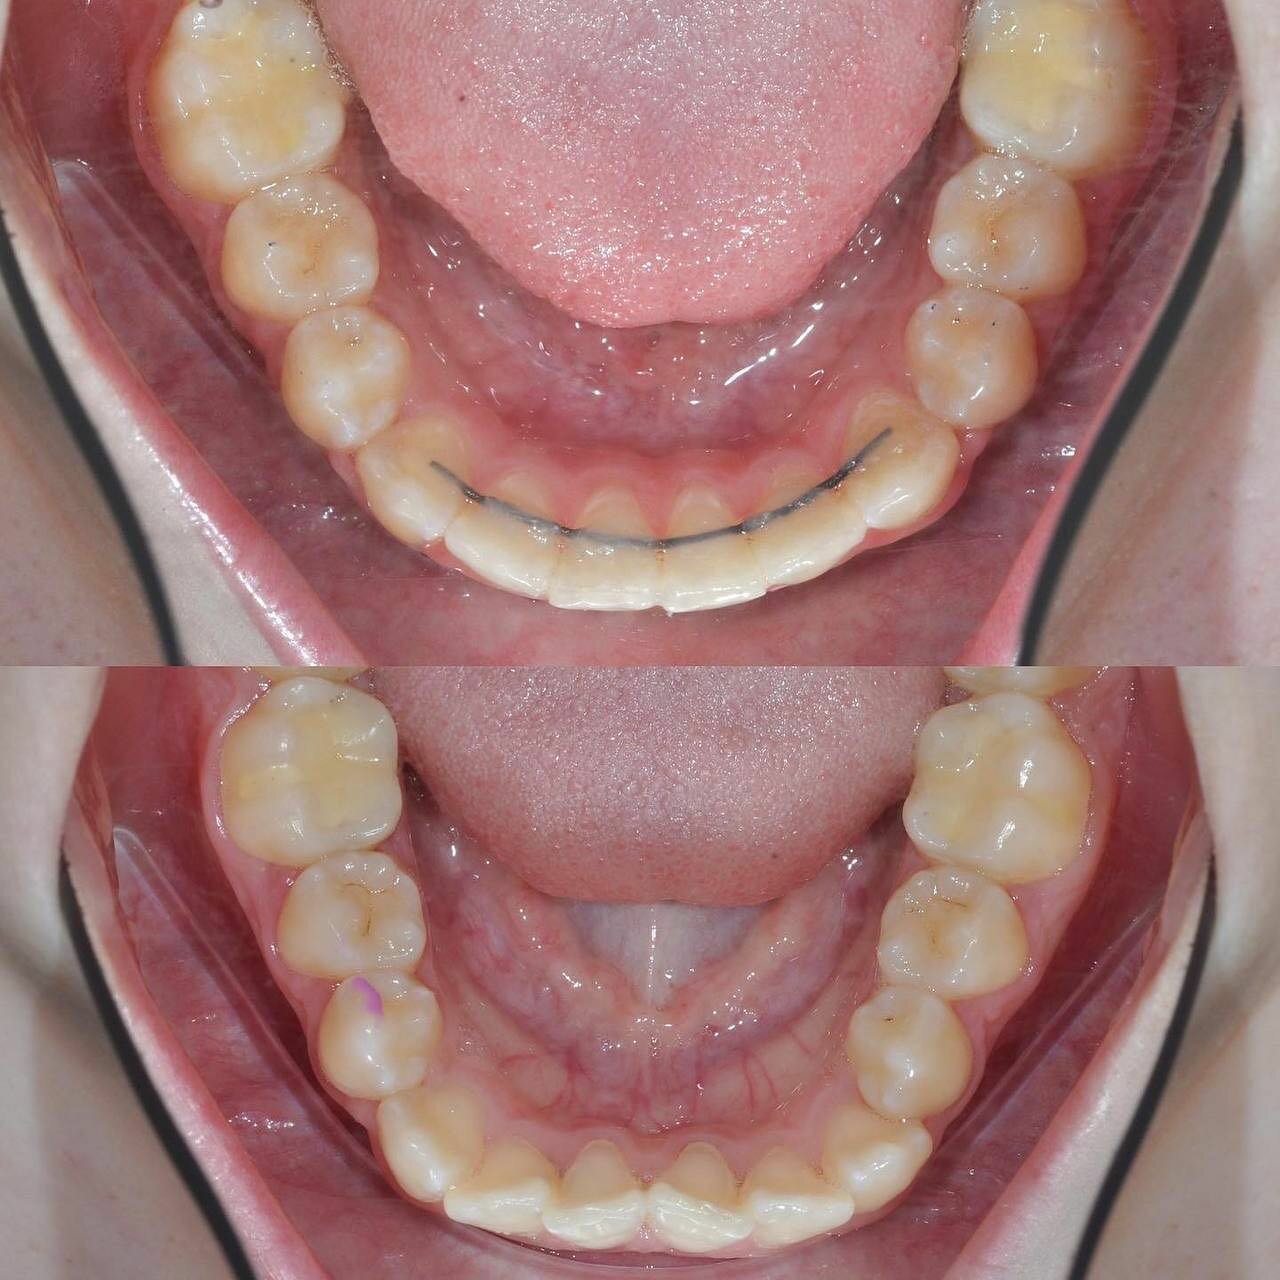

- ортодонтия

- брекеты

- гигиена полости рта

- Безболезненная профессиональная гигиена полости рта.

Приходила на прием в клинику для профессиональной гигиенты полости рта. Всё сделали аккуратно и совершенно безболезненно. После процедуры дали нужные рекомендации. Отличная клиника, всем рекомендую.